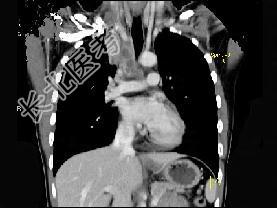

- 单项选择题男,21岁, 干咳,盗汗一月伴消瘦, CT如图,应先考虑为 ( )

A、右上肺结核并纵隔淋巴结核

B、纵隔型肺癌并纵隔淋巴结核转移

C、淋巴瘤

D、右上肺上沟瘤

E、右上肺不张